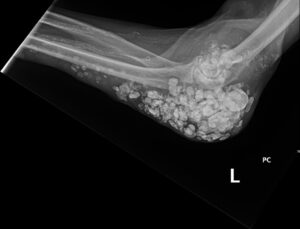

Calcinosis Cutis. Elbow XR, Lateral. JETem 2025

Calcinosis Cutis. Elbow XR Lateral. JETem 2025